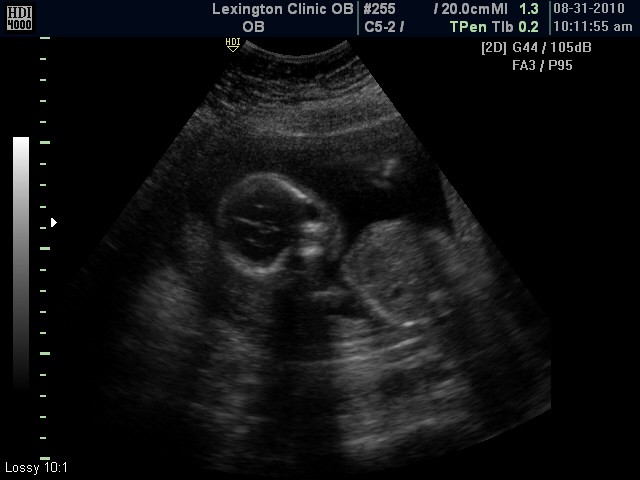

We had the big, important ultrasound and it's a........................................

BOY!!!!

Here are some of the pics from our ultrasound today.

Definitely a boy!

Front of face

Waving hello (see hand on right side)

Side profile of face